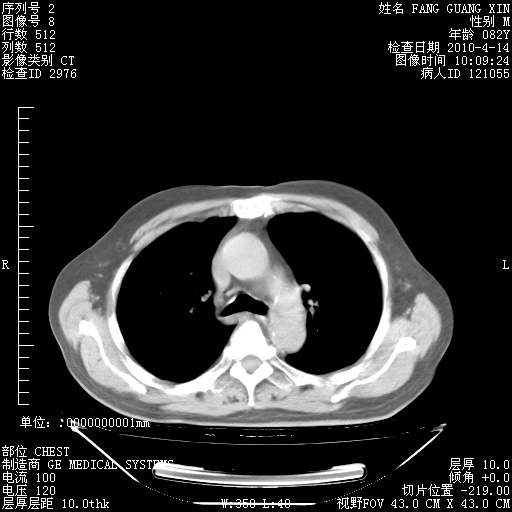

4月14日肺部CT

肺部CT平扫未见异常。